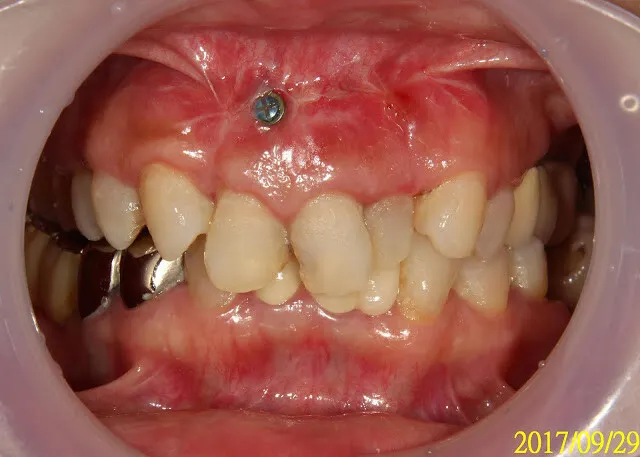

假牙材質4臨床案例---上門牙車禍+雕蠟模型